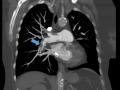

Tromboembolismo pulmonar

Fev de 2016.

Tromboembolismo pulmonar em paciente com câncer de mama

17.974